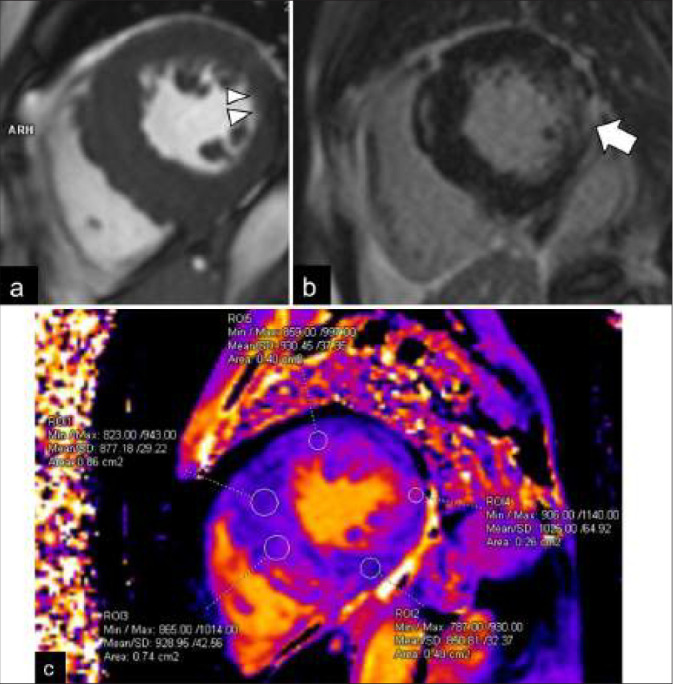

Fabry disease (FD) is a rare X-linked lysosomal storage disorder. Cardiac involvement is frequent in the classic phenotype and late-onset cardiac variant of FD. It is challenging to distinguish FD cardiomyopathy from other forms of unexplained left ventricular hypertrophy, especially in those patients without extracardiac manifestations. Cardiac magnetic resonance imaging is an essential imaging modality for the quantitative and qualitative assessment of FD cardiomyopathy. It helps to monitor disease progress and allows early disease detection in the mild form or subclinical cardiac phenotypes. This review illustrates the characteristic imaging features of FD cardiomyopathy in cardiac MRI, aiming to enhance the awareness of this disease entity among the scope of unexplained cardiomyopathy and promote timely enzyme replacement therapy for patients.